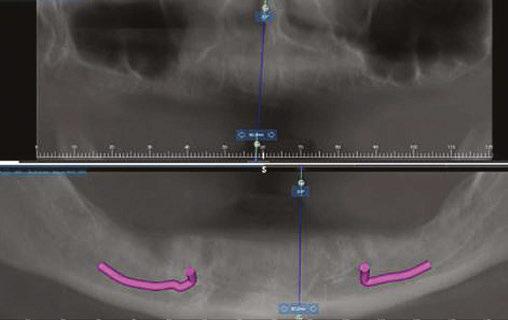

Figure 3: Preoperative panographic view of the maxillary and mandibular arches from the CBCT scan demonstrating anatomy that will impact implant placement Figure 4: Extraoral scan of the full maxillary and man dibular dentures that patient presented with, which she was unable to wear due to a significant gag reflex Figures 5A and 5B: Virtual planning of implant placement in the maxillary arch Figures 6A and 6B: Virtual planning of implant placement in the mandibular arch

A CBCT scan was taken and panoramic views of the maxilla and mandible evaluated (Figure 3). Bilateral pneumatization of the maxillary sinus was noted, but adequate bone height was present between the premolars for implant placement to support an All-on-X hybrid prosthesis. In the mandibular arch, sufficient height was available between the mental foramen bilaterally and over the inferior alveolar nerve for implant placement to also sup port an All-on-X fixed hybrid prosthesis. A discussion was held with the patient that implants could be placed in both arches that would allow restoration with fixed prosthetics. Should sufficient insertion torque be achieved at the time of implant placement, a screw-retained hybrid provisional prosthesis would be placed and worn for several months during healing after which a final prosthesis would be fabricated. The patient would also be able to do a “trial-run” of the esthetics with the provisional prosthesis, with any requested modifications made when the final prosthesis was designed and fabricated. The treatment plan included six implants in each arch to support the planned hybrid prosthe ses. The patient was informed that reduction of the crestal bone would be required to achieve a flat ridge for adaptation of the prosthesis to the ridge as well as to provide adequate interarch space for the final prosthesis. The patient accepted the treatment plan. An intraoral scan of the arches was performed with Medit i500 (Medit Corp, Seoul, Korea) as well as the current complete arch maxillary and mandibular dentures (Figure 4). The patient was dismissed and scheduled for the surgical appointment.

The scans were imported into the planning software (Real GUIDE™, Allston, Massachusetts) and merged with the CBCT scan to allow implant planning. The maxillary arch was planned for implants at six sites, including tilted implants mesial to the maxillary sinus bilaterally to avoid the need for sinus augmen tation and allow more distal placement of the implant platform for a better anterior/posterior (A-P) spread (Figure 5A). ULT implants were planned as follows: No. 3 (3.75 x 11.5 mm), No. 6 (3.75 x 11.5 mm), No. 8 (3.75 x 11.5 mm), No. 9 (3.75

The mandibular arch was then planned for seven possi ble implants with the extra implant beyond what was initially planned should the short posterior implant on the patient’s left have less than ideal initial stability to provide better stability of the provisional prosthesis (Figure 6A). Ditron Dental ULT implants were planned as follows: No. 19 (3.75 x 11.5 mm), No. 20 (3.75 x 11.5 mm), No. 22 (3.75 x 11.5 mm), No. 24 (3.75 x 11.5 mm), No. 25 (3.75 x 11.5 mm), No. 27 (3.75 mm x 10 mm), and No. 30 (3.75 x 11.5 mm) (Figure 6B). A replica of the current dentures was fabricated to be used as a surgical guide, and the center of the replica was removed with a lab bur to create a zone for the implants to emerge to ensure they would be within the proper prosthetic zone (Figure 7).